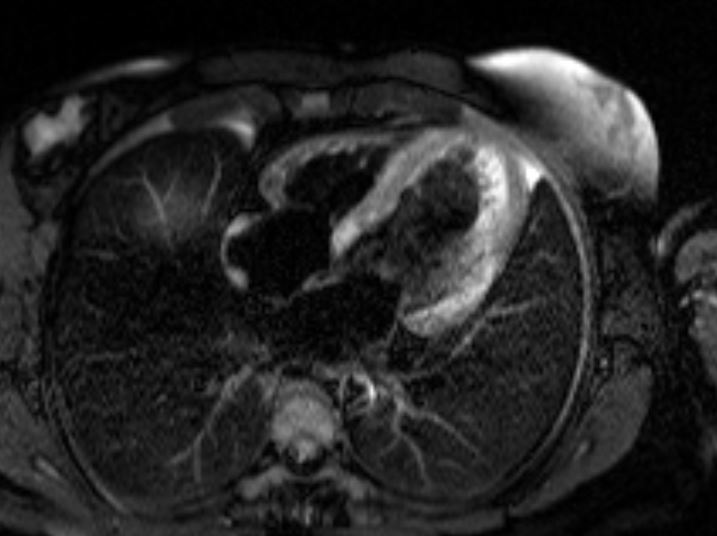

Case Presentation: A 32-year old woman with past medical history significant for myasthenia gravis (MG), polymyositis, and systemic lupus erythematosus (SLE) was admitted to the hospital for evaluation of non-sustained ventricular tachycardia (NSVT) discovered during 72-hour Holter monitoring. Patient had been experiencing palpitations with heart rate up to 200 beats per minute recorded on her smart watch, associated with substernal chest pressure and exertional dyspnea, for one month. Her medications included pyridostigmine, mycophenolate mofetil and prednisone; she was also receiving monthly plasmapheresis due to severe exacerbation of myasthenia symptoms 4 months prior. Labs on presentation were significant for troponin elevation at 10.6 ng/mL (normal: <0.04), BNP 462, hypogammaglobulinemia, hypocomplementemia, and normal ESR and CRP. CT Angiogram of the coronaries was negative for atherosclerosis. Hypokinesis of the inferior myocardial wall was noted on echocardiogram. Cardiac MRI showed reduced left and right ventricular systolic function, with a left ventricular ejection fraction (LVEF) of 41%. Multiple biventricular areas of myocardial enhancement were present, indicating an acute injury. Infectious workup, including a full viral panel, was negative. Review of skeletal muscle biopsy performed at an outside hospital showed giant cells, inconsistent with a diagnosis of polymyositis. Patient had previously 2 positive and 1 negative dsDNA antibody tests; repeat anti-dsDNA using a crithidia assay, which has the highest specificity for SLE, was negative. Hypocomplementemia and hypogammaglobulinemia were attributed to recent plasmapheresis. Further workup showed positive acetylcholine receptor binding, blocking, and modulating antibodies, as well as positive anti-titin and anti-striational muscle antibodies, all seen in MG. No thymoma was present on Chest CT. Treatment with intravenous high dose steroids and mycophenolate was initiated with resolution of ventricular arrhythmias. Plasmapheresis was switched to weekly intravenous immunoglobulin (IVIG) administration. Amiodarone was started for arrhythmia control. Follow-up echocardiogram 7 days after treatment initiation showed improved LVEF of 45-49%.